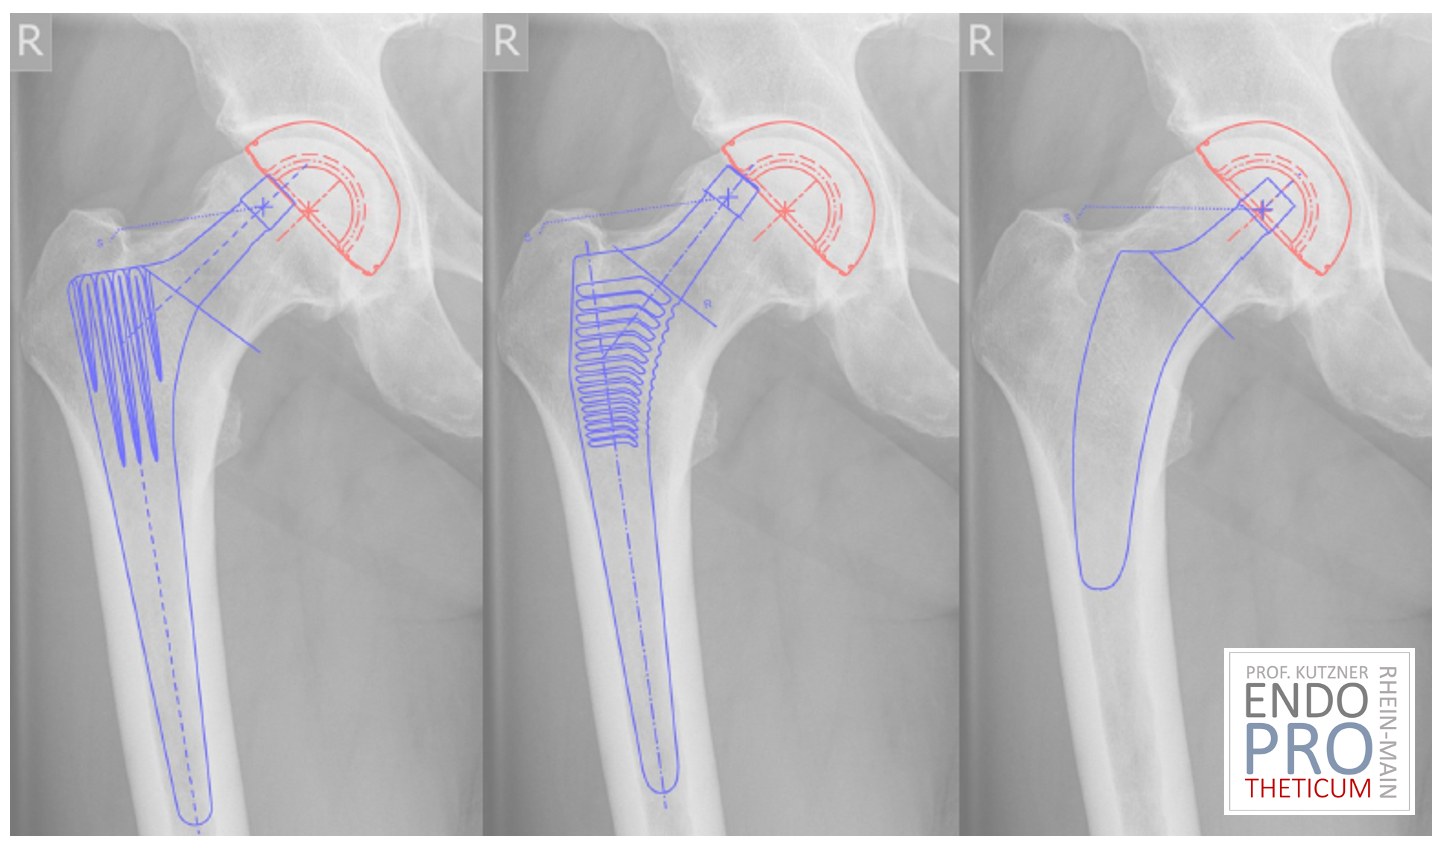

Имплантация протеза с коротким стержнем требует:

- точной планировки

- понимания анатомии

- опыта метафизарной фиксации

В отличие от стандартного стержня, позиционирование менее толерантно к ошибкам.

Поэтому специализация имеет решающее значение.